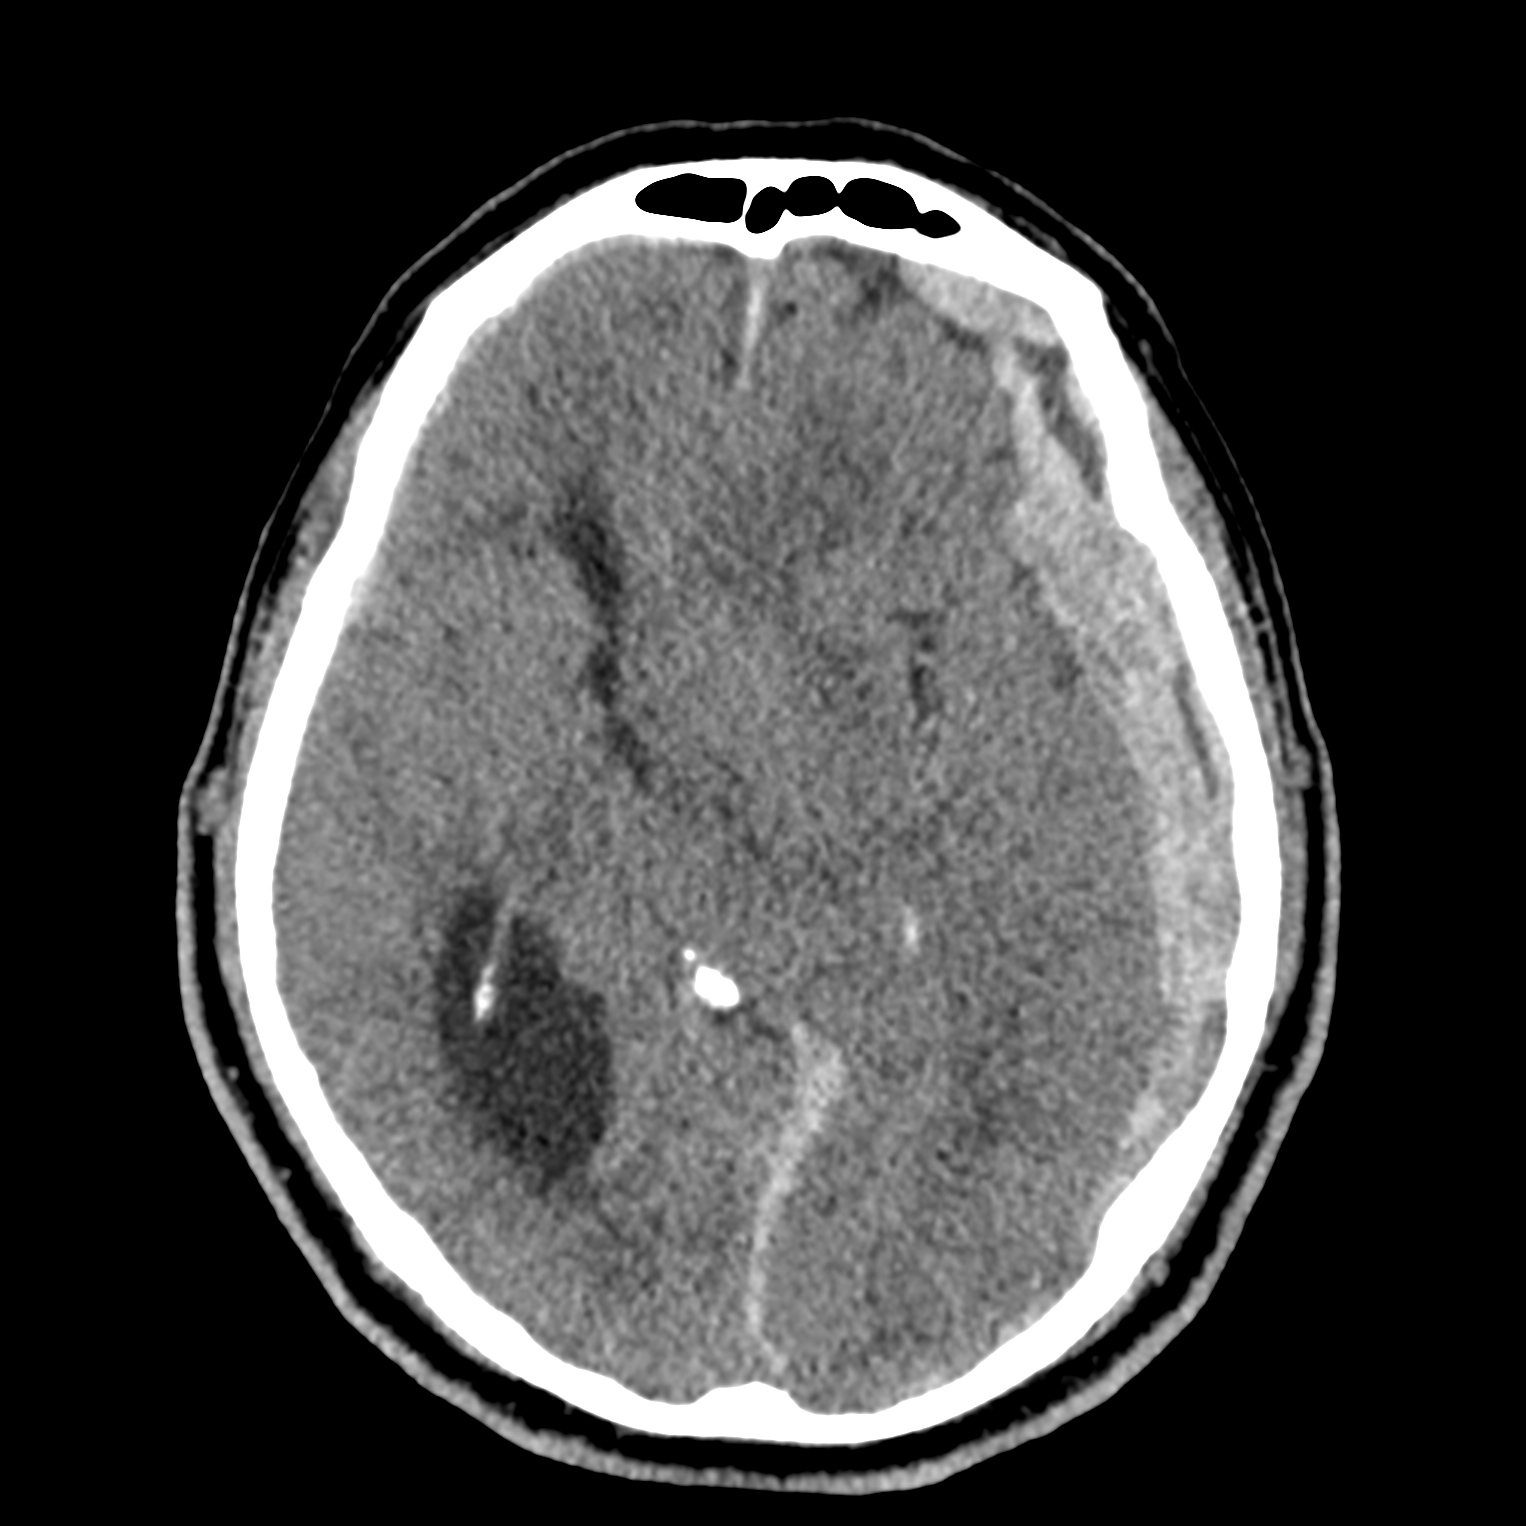

ちなみに画像診断とは、CTやMRIなどの画像を見て、正常か異常か、異常であればそれが何なのかを診断する仕事です。

Case courtesy of Andrew Dixon, Radiopaedia.org. From the case rID: 32383

医療従事者でなければ何のメリットも無いかもしれないのですが、実際の画像を自分でスクロールしながら学ぶことができるというのは、ものすごく大きなことだと思います。

さらに症例の解説を付け加えたら、読影能力アップのための強力なツールになるのではないかと期待しています。